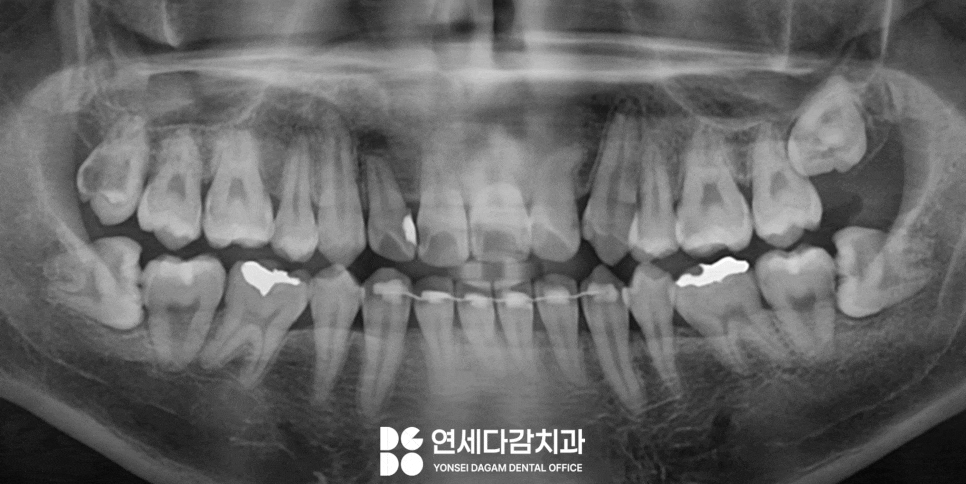

매복되어 있을 때는

잇몸 안에 묻혀 있어 정확한 위치를

육안으로 파악하기엔 어렵습니다.

따라서 CT 촬영이 필수이며

이를 통한 3차원적인

구조 분석이 중요합니다.

오금역 치과 에서는 이때

치아의 정확한 위치와 각도를

파악하고,

주변 구조물과의 위치 관계를

살펴보는 과정을 시행하게 됩니다.